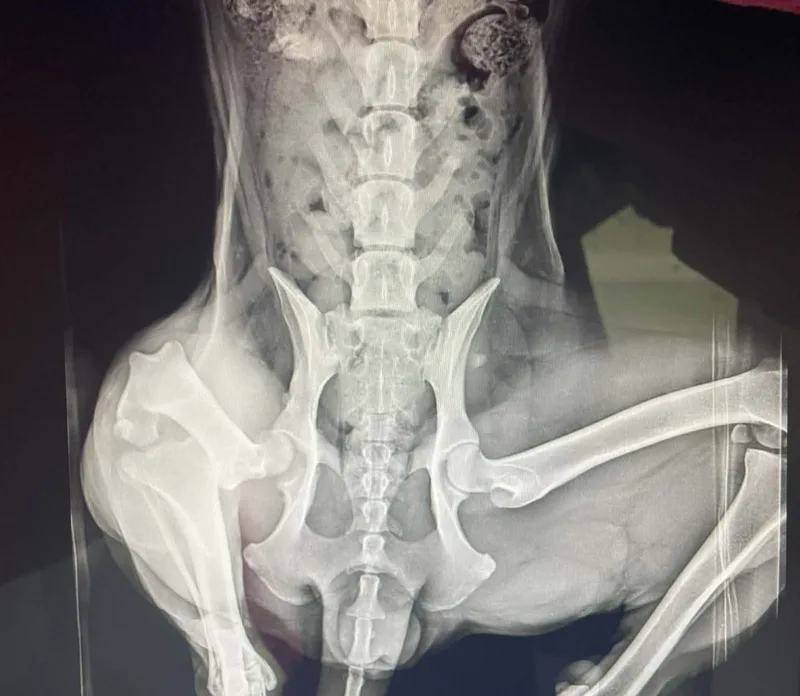

Female Chipped OSS (Ovary Sparing Spay) Please note: dog will have a heat cycle still but not bleed due to her uterus being removed. This allows for the dog to still have all the wonderful health benefits of having hormones without getting pregnant. Heat smell can be mitigated by giving the dog chlorophyll during her cycles so as to not attract male dogs. More info on hormone sparing sterilizations on our website. Current on vaccines and deworming We believe Maisie was dumped near the corner of N. Kulani. She was terrified and would not allow anyone to approach her. On December 7th, we were able to safely catch her using a dog trap, and she has been with her foster family in Keaau ever since. Shortly after arriving in foster care, it became clear that something wasn’t right with her leg. X-rays revealed that this sweet girl had a dislocated hip. Once she was given pain medication, Maisie immediately began playing like the puppy she truly is—showing just how much discomfort she had been living with. Our options were amputation or an FHO (femoral head ostectomy) surgery, and we chose surgery in order to save her leg. Thanks to generous fundraising efforts and overwhelming community support, Maisie was able to receive the surgery she needed. She is still in the healing process, but we are now accepting applications for when she is ready for adoption. 🤍 Maisie does not do well when crated while left alone. She has managed to break or chew her way out of standard crates, so unless an impact crate is available, she will need to be secured on a lead in the yard when her owners are away. When people are home, she does very well—even in a crate. When left alone, her puppy curiosity can lead to some mischief, but with patience, training, and time, she is expected to grow out of this phase. We believe Maisie is under a year old, so she is still very young. She currently weighs around 35 pounds and is not expected to grow much larger. She does not appear to have a high prey drive and is likely to do well with cats and chickens. She is mostly potty trained with the occasional accident, rides great in the car, walks nicely on leash, and gets along well with all other dogs. 🐾